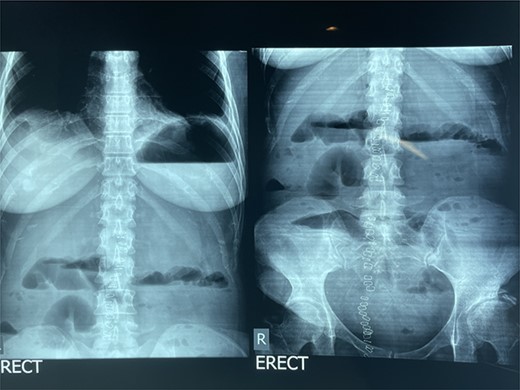

Over the next 24 h, the patient developed obstipation, worsening resistant fever and hypotension (80/42 mmHg). On examination, the abdomen was distended, nontender and rigid all over. The nasogastric tube products were greenish with minimal food content. An erect abdominal X-Ray was ordered, revealing worsening distended bowel with air-fluid levels and air under the diaphragm (see Fig. 1).